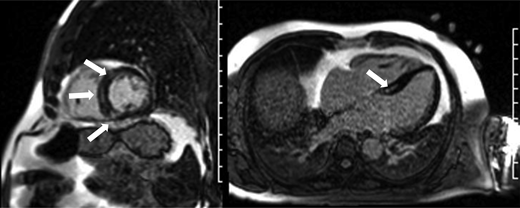

As cardiotoxicity may not manifest until decades after cancer treatment, lifelong surveillance of at-risk childhood cancer survivors is recommended.4  Serial echocardiography is generally used to monitor cardiac function during and after pediatric cancer therapy due to its widespread availability, lack of invasiveness, and lack of patient-related barriers such as poor renal function or claustrophobia.18  While most echocardiograms have typically focused on 2-dimensional measurements of left ventricular systolic function such as ejection fraction (EF) and fractional shortening (FS), 2-dimensional echocardiography is limited by both reliance on geometric assumptions of left ventricular morphology and greater inter- and intraobserver variability when compared with 3-dimensional echocardiography or cardiac magnetic resonance (CMR) imaging.19  Changes in EF and FS are also felt to represent later markers of cardiotoxicity, and earlier markers of disease, such as changes in myocardial strain, may enhance the ability of echocardiography to detect earlier cardiotoxicity in cancer survivors (Figure 3).20  Nevertheless, acute drops in EF or FS during therapy may be important prognostically, with recent data from pediatric patients with AML showing that those with acute cardiotoxicity (>10% of patients) had an approximate 60% increased relapse and mortality risk (Figure 4).21  However, detailed information on treatment modifications following acute cardiotoxicity was not captured, which precluded the ability to determine if lower cumulative anthracycline exposure mediated the association between cardiotoxicity, relapse, and mortality risk.

Figure 3.

Example of borderline left ventricular systolic function (ejection fraction of 50%-55%) per 2-dimensional echocardiogram supplemented with myocardial strain measurements, which show abnormal global longitudinal strain (−12.3%) 15 years after cancer treatment. Patient was originally treated for Hodgkin lymphoma per Children's Oncology Group protocol AHOD0031 with doxorubicin, bleomycin, vincristine, etoposide, cyclophosphamide, and neck radiation.